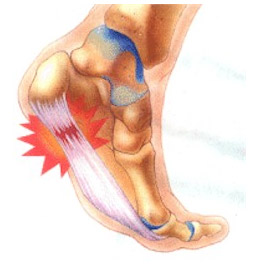

La temida fascitis plantar cuando se cronifica en el tiempo pasa a denominarse fasciosis ambas son patologías musculo-ligamentosas que aparecen en la planta del pie y llegan a ser incapacitantes (el dolor suele darse en el momento del despegue en la marcha y/o carrera). Estas patologías pueden ser debidas y/o estar presentes a la vez que el espolón calcáneo (osificación anómala en el talón). En éste caso el dolor por espolón calcáneo se da con el primer paso, al choque de talón con el suelo.

- Infiltración en Fascia Plantar